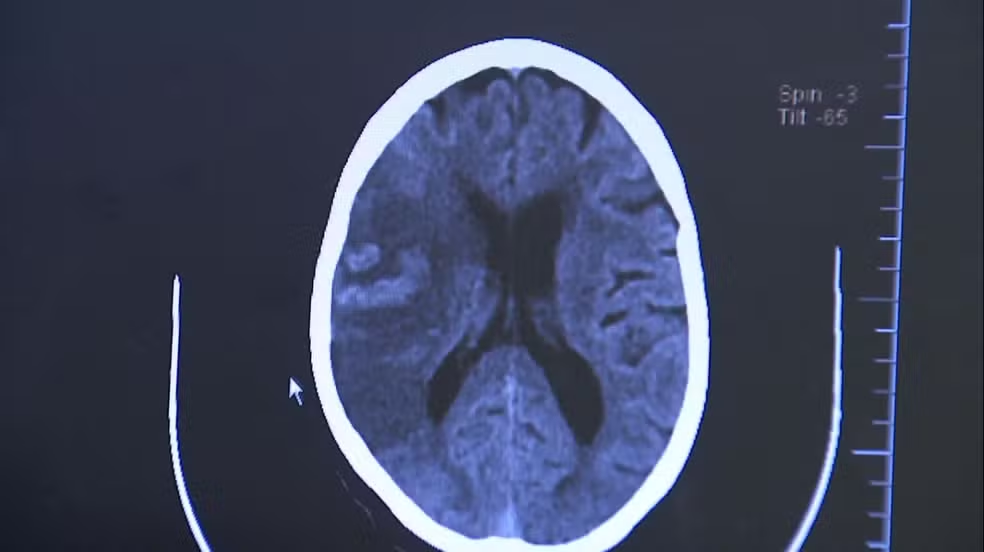

Tipos de AVC

- Isquêmico (85% dos casos) – ocorre quando há entupimento de um vaso sanguíneo que leva sangue ao cérebro. Está ligado à pressão alta e a doenças cardíacas, como a fibrilação atrial, que pode formar coágulos e bloquear artérias cerebrais.

- Hemorrágico (15% dos casos) – acontece quando há rompimento de um vaso, provocando sangramento no tecido cerebral. É menos comum, mas mais grave, com risco elevado de sequelas e morte.

“Durante o AVC isquêmico há um bloqueio na artéria, levando à falta de sangue e morte das células cerebrais. Já no hemorrágico, o sangue extravasa por ruptura de um vaso”, explica o neurocirurgião Feres Chaddad, professor da Universidade Federal de São Paulo (Unifesp) e chefe da neurocirurgia da BP – A Beneficência Portuguesa de São Paulo.